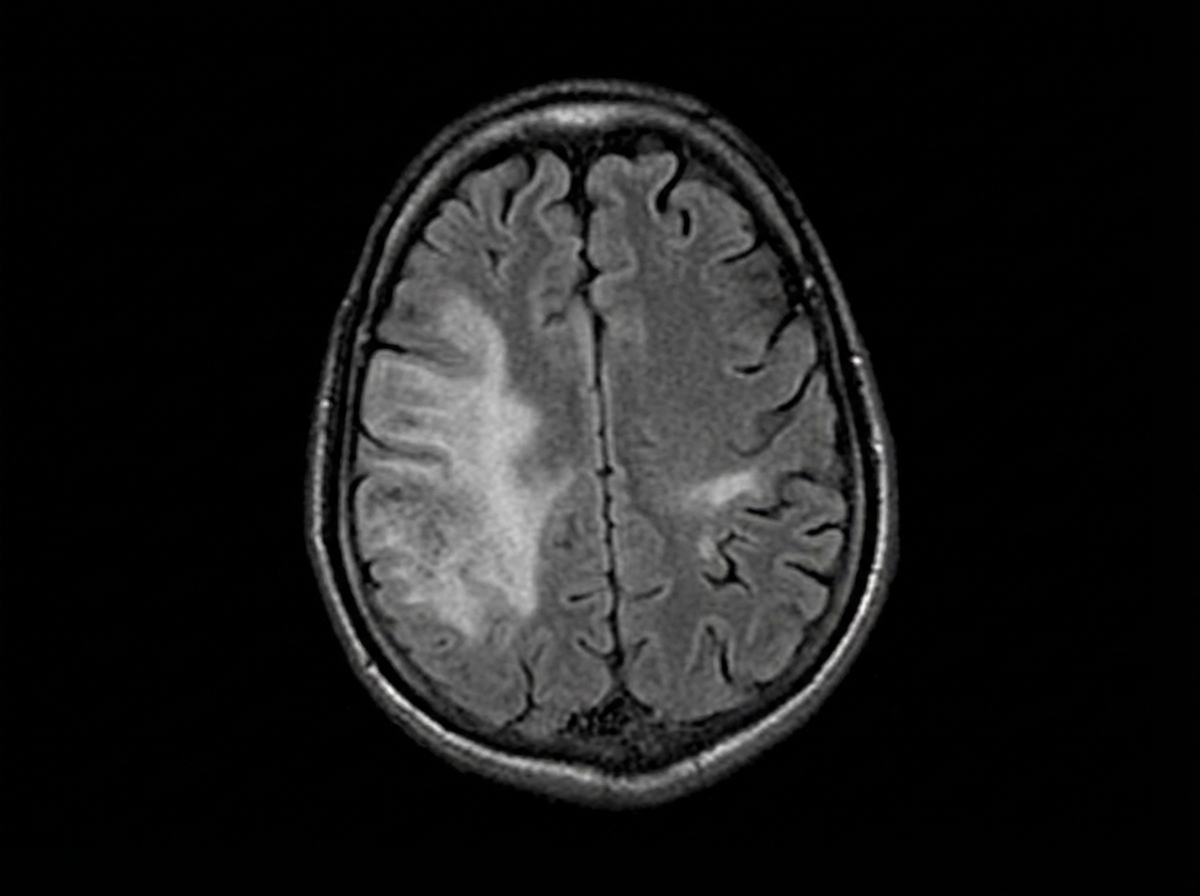

A 44-year-old man is brought to the emergency department by his daughter for a 1-week history of right leg weakness, unsteady gait, and multiple falls. During the past 6 months, he has become more forgetful and has sometimes lost his way along familiar routes. He has been having difficulties operating simple kitchen appliances such as the dishwasher and coffee maker. He has recently become increasingly paranoid, agitated, and restless. He has HIV, hypertension, and type 2 diabetes mellitus. His last visit to a physician was more than 2 years ago, and he has been noncompliant with his medications. His temperature is 37.2°C (99.0°F), blood pressure is 152/68 mm Hg, pulse is 98/min, and respiratory rate is 14/min. He is somnolent and slightly confused. He is oriented to person, but not place or time. There is mild lymphadenopathy in the cervical, axillary, and inguinal areas. Neurological examination shows right lower extremity weakness with normal tone and no other focal deficits. Laboratory studies show: Hemoglobin 9.2 g/dL Leukocyte count 3,600/mm3 Platelet count 140,000/mm3 CD4+ count 56/µL HIV viral load > 100,000 copies/mL Serum Cryptococcal antigen Negative Toxplasma gondii IgG Positive An MRI of the brain is shown below. Which of the following is the most likely diagnosis?